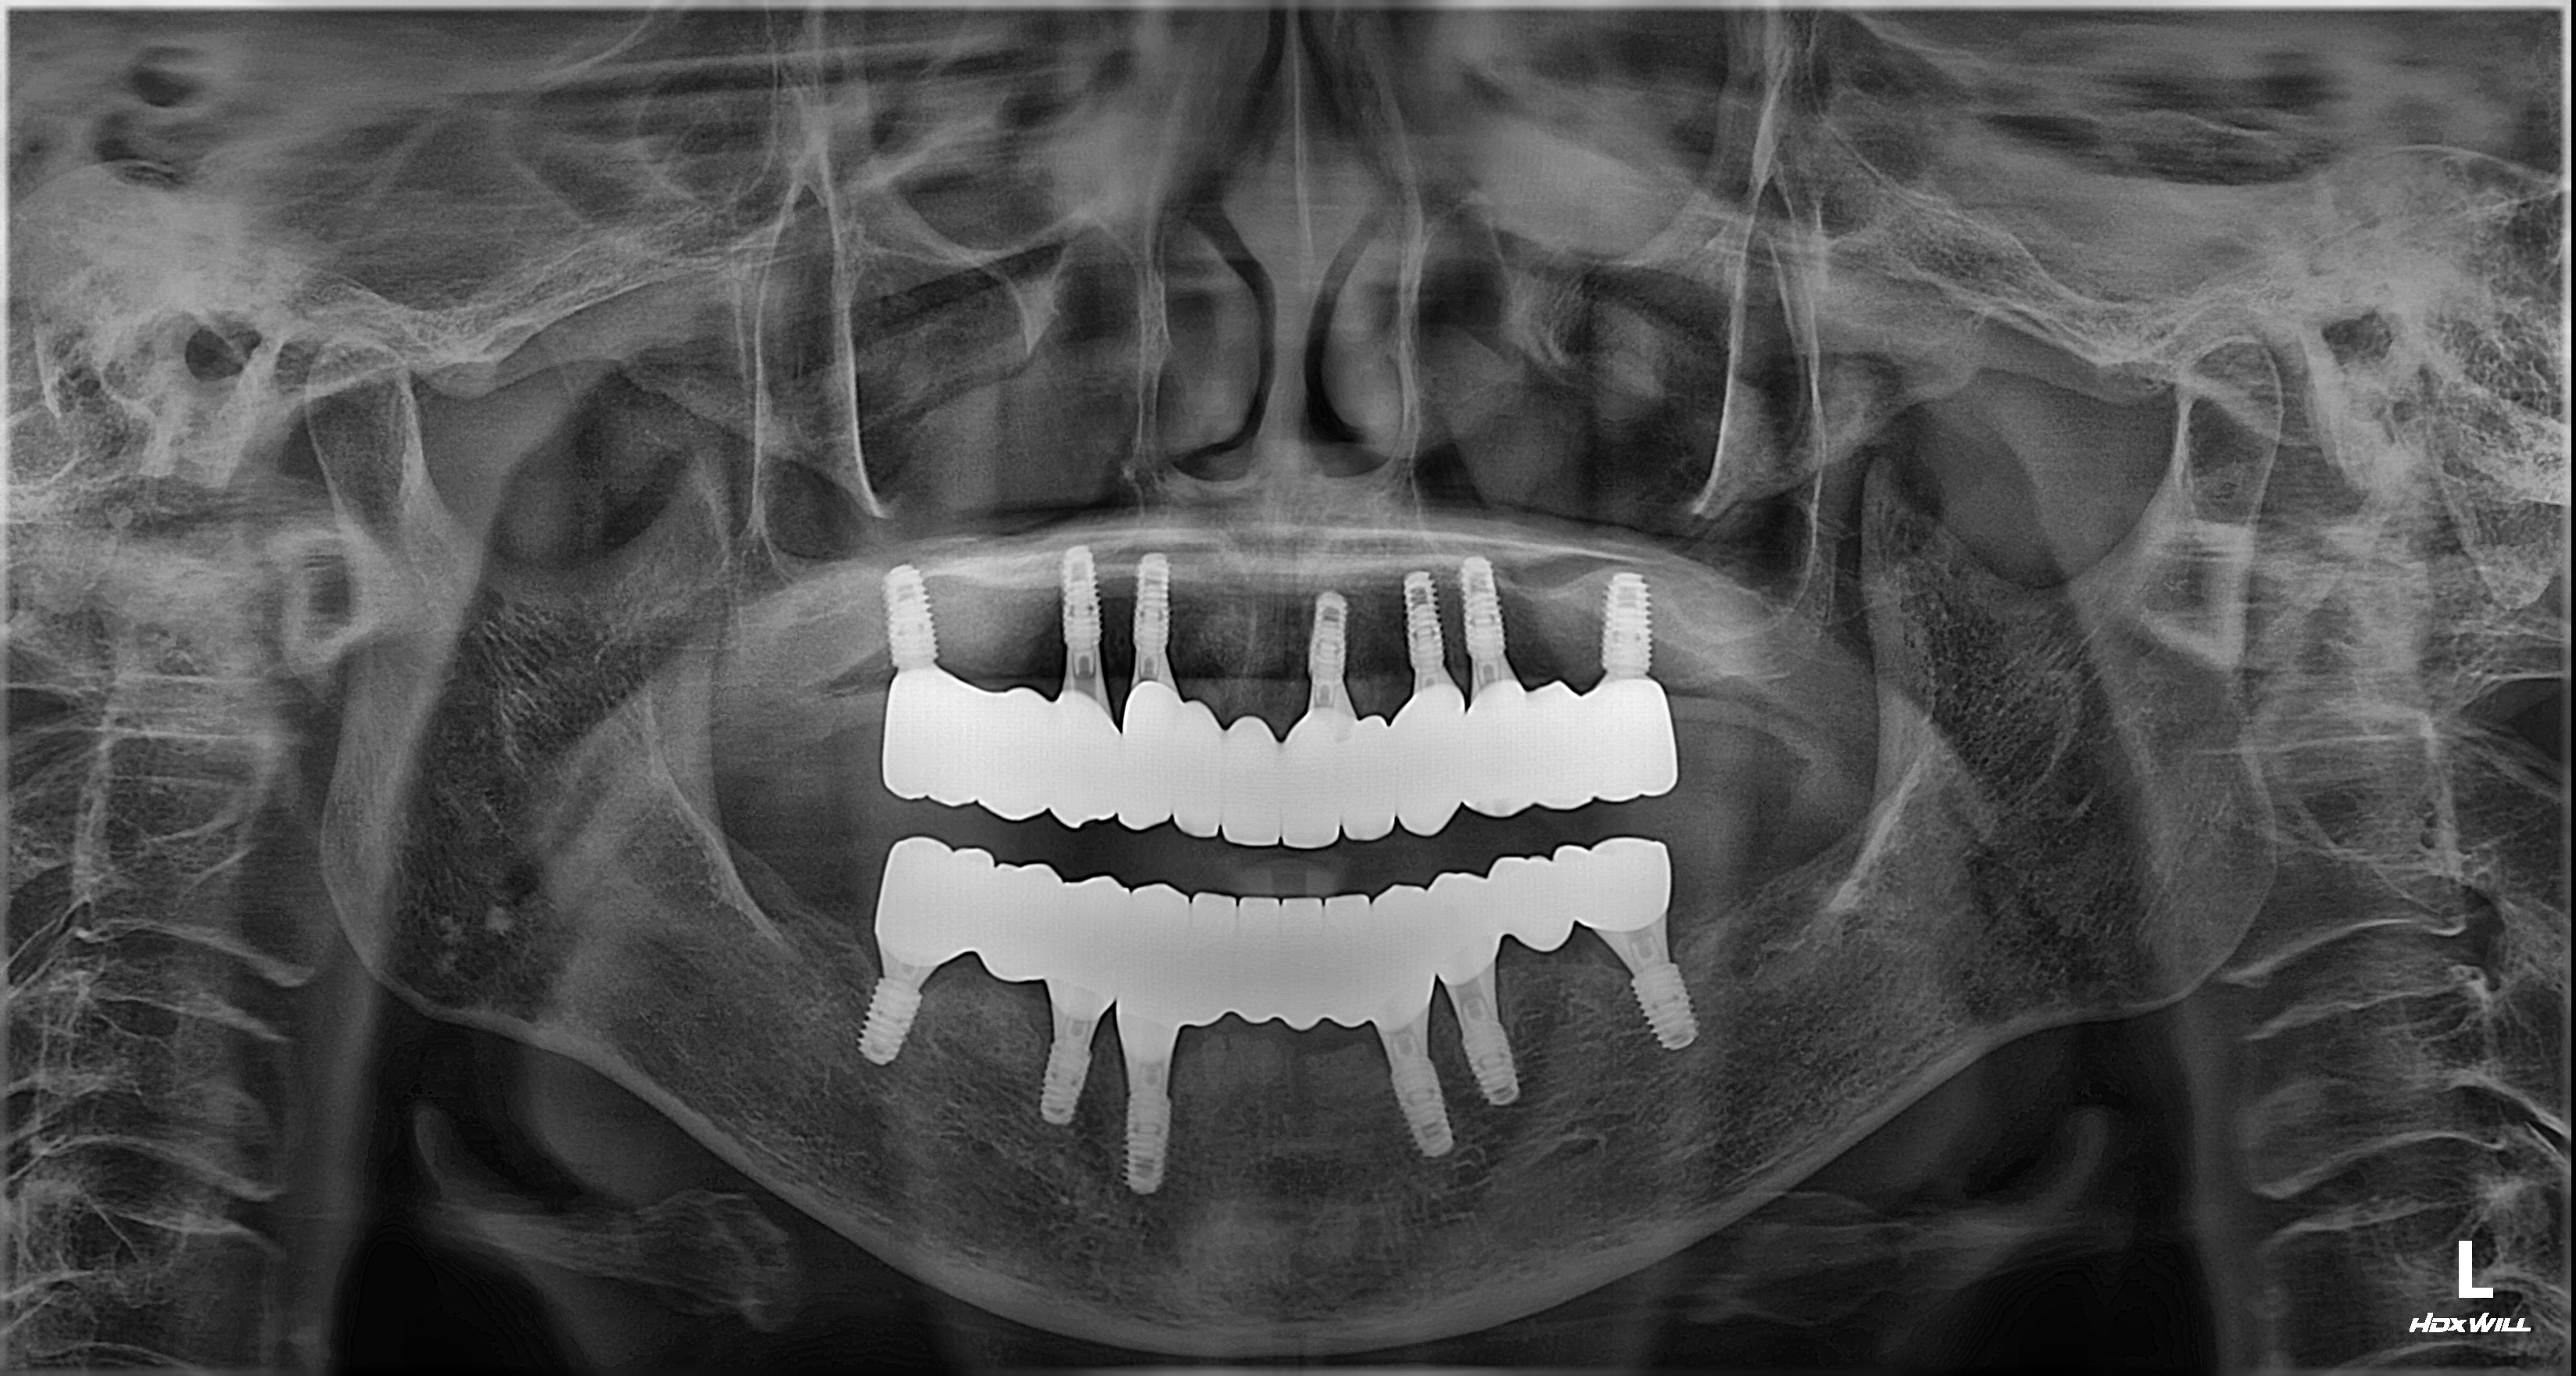

촬영일시: 2025.12.31 [ 치료기간: 2025년 06월 05일 ~2025년 12월 31일 ] ※ 365서울앞선치과의원의 모든 컬럼은 각 진료과 의료진이 직접 작성합니다. 365서울앞선치과의원 임상 케이스 게시물은 환자분께 의학적으로 정확하고 상세한 정보를 드리기 위해 각 진료과 의료진이 직접 작성하며, 모든 증례 사진은 본원 의료진이 직접 시술한 증례를 촬영한 것으로, 의료법 제23조, 제56조에 의거하며 환자분의 동의를 얻어 포스팅에 사용하였습니다. 또한 해당 케이스는 본 환자분의 치료 결과이며, 환자 상태에 따라 치료의 결과는 달라질 수 있습니다. |